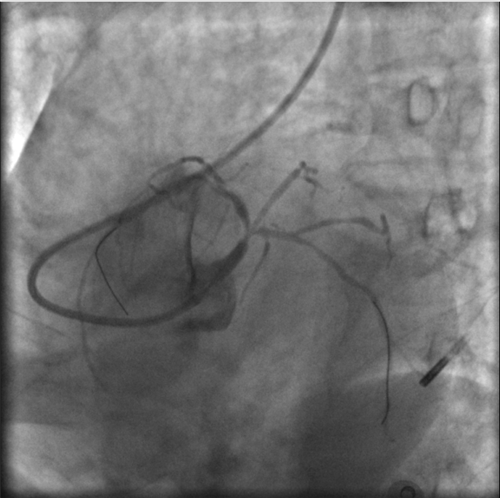

快速完成右側(cè)橈動(dòng)脈穿刺,上造影導(dǎo)管受阻后,行肱動(dòng)脈造影,發(fā)現(xiàn)右側(cè)肱動(dòng)脈重度狹窄。

左主干完全閉塞

小心操作導(dǎo)絲及導(dǎo)管,艱難到達(dá)主動(dòng)脈根部,但導(dǎo)管難以“到位”左冠口,“冒煙”見(jiàn)左主干居然完全閉塞了。

右冠近段嚴(yán)重狹窄,未見(jiàn)右向左的側(cè)枝循環(huán)

再行右冠造影,右冠近段也嚴(yán)重狹窄,未見(jiàn)右冠向左冠的側(cè)枝循環(huán)。

在場(chǎng)的醫(yī)護(hù)人員都大吃一驚,原來(lái)他們遇到了離死亡最近的血管堵塞——左主干急性閉塞。由于左冠狀動(dòng)脈主干的血管支配了整個(gè)左心系統(tǒng),一旦血流被急性阻斷,整個(gè)心臟就會(huì)失去2/3的血液供應(yīng)。因此,左主干急性閉塞起病急,進(jìn)展快,死亡率極高,是一種非常高危的胸痛疾病。